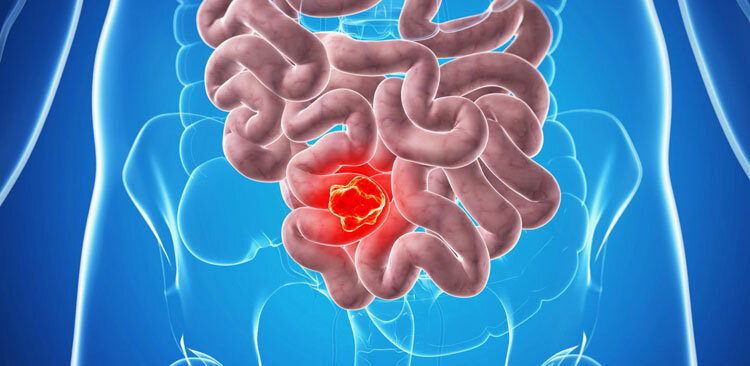

1. Рак

Рак – болезнь, преследовавшая человека, является одной из страшных болезней века. Вызывается множественными причинами, например, радиоактивными излучениями и химическими веществами, к которым относятся органические красители, выхлопные газы, некоторые пищевые консерванты. Хроническая усталость и стресс тоже, как ни странно, запускают процесс роста раковых клеток. Рак может развиваться из-за вирусов папилломы и генитального герпеса, передающиеся половым путём. Так что беспорядочная, незащищённая половая жизнь, которая в наше время достаточно распространённое явление, является серьезным фактором риска.